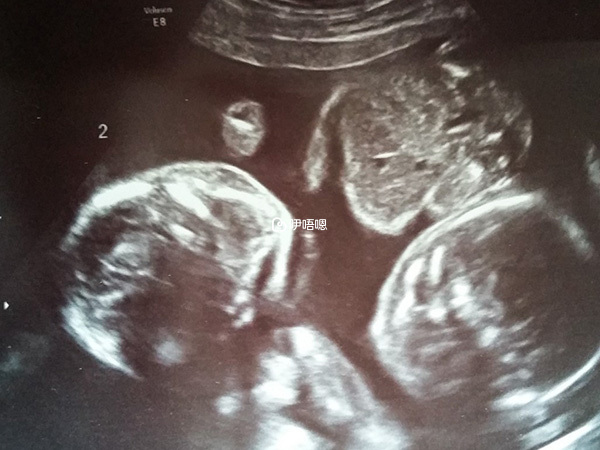

8月1日:驗血,孕酮>60,hcg>10000從7月24日開始,我偶有很淺的咖啡色分泌物,覺得和注射黃體酮的情況有關,只要我的肌肉吸收不好,出現了硬結,很快就有咖啡色分泌物,很規律。問了醫生,醫生說正常的。8月8日:移植後28天,醫院B超結果為雙孕囊。其中一個2.1*2.1,有胎芽胎心,另一個3.2*1.8,隱約可見胎芽胎心,要求一週後再次B超。我準備10天后再去,正好兩個月的時候。從移植後20天開始有妊娠反應,不吐,上午沒事,從中午開始到晚上睡前持續噁心。

但是奇怪的是我居然沒有特別難過,只是覺得絕這樣了,認命吧。老公火速開車送我去婦產醫院,醫生看了我帶去那兩大塊東西淡淡的說,“不是胚胎,好像是血塊,打個B超吧。”我死了的心又活泛起來,老公馬上去買水,我憋了半個多小時的尿後開始B超。結果是兩個寶寶還在,胎心也很好,兩個胎芽大小比較均勻,還比一週前長大了1CM。

9月17日:7點鐘從家裡出發,7點半準時到b超排號處。終於排到了上午的號,27號。等到10:20終於輪到我了。結果還不錯,兩個寶寶大小和孕週一致,胎心都很好,NT一個是1.5cm,一個是1.6cm,排除了風險,比較滿意。預產期4月1日,但是雙胎的話估計一定會早產。